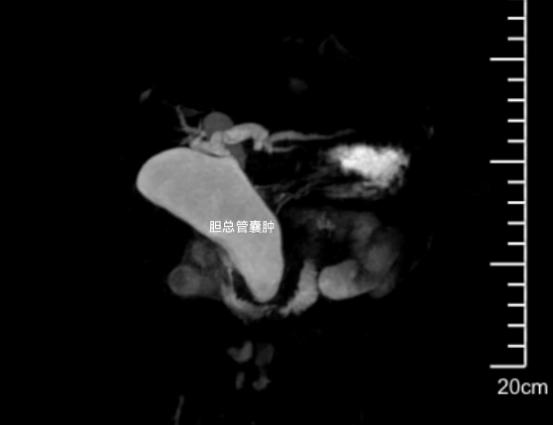

9月1日,我院水南院區(qū)兒科急診來了一名年僅2歲的腹痛發(fā)熱寶寶,其當(dāng)?shù)蒯t(yī)院B超檢查發(fā)現(xiàn)肝區(qū)有囊性回聲,轉(zhuǎn)來我院檢查。入院后完善腹部影像學(xué)檢查提示,小寶的肝總管及膽總管明顯擴(kuò)張(最寬處達(dá)3.1cm),診斷為先天性膽總管囊腫。該疾病屬于先天性結(jié)構(gòu)發(fā)育異常,是兒童常見的膽道畸形,若不及時干預(yù),易引發(fā)膽汁淤積、胰腺炎甚至癌變風(fēng)險,感染時癥狀加重,通過手術(shù)進(jìn)行結(jié)構(gòu)重建是根治這種疾病的最佳方案。